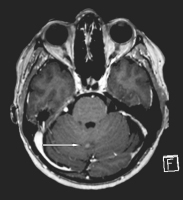

Abbildung 2: Axiale T1-gewichtete Sequenz des Gehirnschädels. Noduläre leptomeningeale Kontrastmittel- aufnehmende Läsion zerebellär rechts paramedian, hinweisend auf eine beginnende Meningeosis carcinomatosa

Keywords: axiale SequenzGehirnschädelMeningeosis carcinomatosaOnkologie